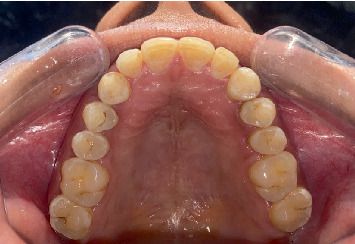

牙齿变色,特别是由于氟中毒,提出了一个显着的审美挑战,许多患者。本文探讨了牙齿漂白和牙釉质微磨损联合使用作为治疗氟中毒引起的变色的有效方法。牙齿漂白是一种广泛应用于减轻外在和内在污渍的方法,在改善变色牙齿的整体外观方面显示出良好的效果。牙釉质微磨蚀,包括机械去除表面牙釉质污渍,可以通过解决更严重或更顽固的变色来提高漂白的有效性。本文综述了这些治疗的机制,它们的临床适应症,以及它们在不同程度的氟牙症患者中的结果。此外,还讨论了潜在的副作用,如牙齿敏感和牙釉质损伤,并强调了减少这些风险的策略。通过结合这些方法,临床医生可以为寻求氟牙美容改善的患者提供更全面,个性化的护理,同时关注美观结果和长期牙齿健康。

Dental discoloration, particularly due to fluorosis, presents a significant aesthetic challenge for many patients. This article explores the combined use of dental bleaching and enamel microabrasion as effective treatments for managing fluorosis-induced discoloration. Dental bleaching, a widely used method for lightening extrinsic and intrinsic stains, has shown promising results in improving the overall appearance of discolored teeth. Enamel microabrasion, which involves the mechanical removal of superficial enamel stains, can enhance the effectiveness of bleaching by addressing more severe or resistant discoloration. The article reviews the mechanisms of these treatments, their clinical indications, and their outcomes in patients with varying degrees of dental fluorosis. Additionally, potential side effects, such as tooth sensitivity and enamel damage, are discussed, emphasizing strategies to minimize these risks. By combining these methods, clinicians can offer more comprehensive, individualized care for patients seeking cosmetic improvements for fluorotic teeth, with attention to both aesthetic outcomes and long-term dental health.